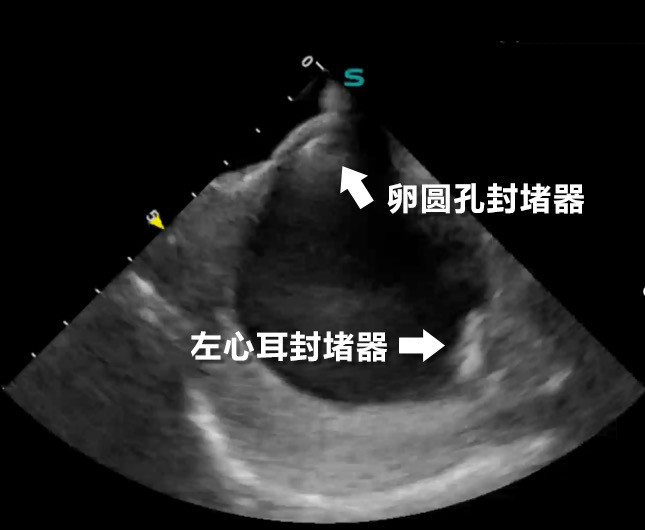

心腔内超声下的双封堵器

手术中,何奔教授团队在腔内超声影像引导下,巧妙通过卵圆孔送入输送鞘,率先植入左心耳封堵器,精准封闭房颤血栓的主要来源。随后,又植入卵圆孔未闭封堵器,成功闭合心脏房间隔的异常通道。术后即刻显示,两枚封堵器位置理想,无残余分流。